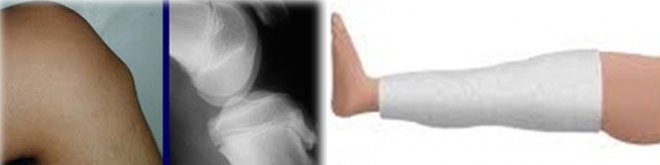

Ο έφηβος, κυρίως παιδιά που ασκούνται πολύ (ποδόσφαιρο, κ.α.) εμφανίζουν στην πρόσθια επιφάνεια του γόνατος μια διόγκωση (η οποία δημιουργεί συχνά και φόβο ότι πρόκειται για όγκο). Η προβολή αυτή είναι συνήθως αμφοτερόπλευρη (συνήθως είναι επώδυνη περισσότερο η μία πλευρά) και λίγο θερμή.

Για επιβεβαίωση χρειάζεται ακτινογραφία των γονάτων σε πλάγια λήξη (Profile) για να αποκλεισθεί η πιθανότητα όγκου (σπάνια μεν, αλλά υπάρχει) και να σταδιοποιηθεί η αλλοίωση για την θεραπεία.

Σε περιπτώσεις που η ακτινογραφία δείχνει ότι ο χόνδρος κινδυνεύει να ξεκολλήσει χρειάζεται ακινητοποίηση του γόνατος με γύψινο νάρθηκα για τρεις εβδομάδες. Στις άλλες περιπτώσεις αρκεί η αποφυγή καταπόνησης με αθλοπαιδιές για 3 μήνες (ποδόσφαιρο, ποδήλατο).